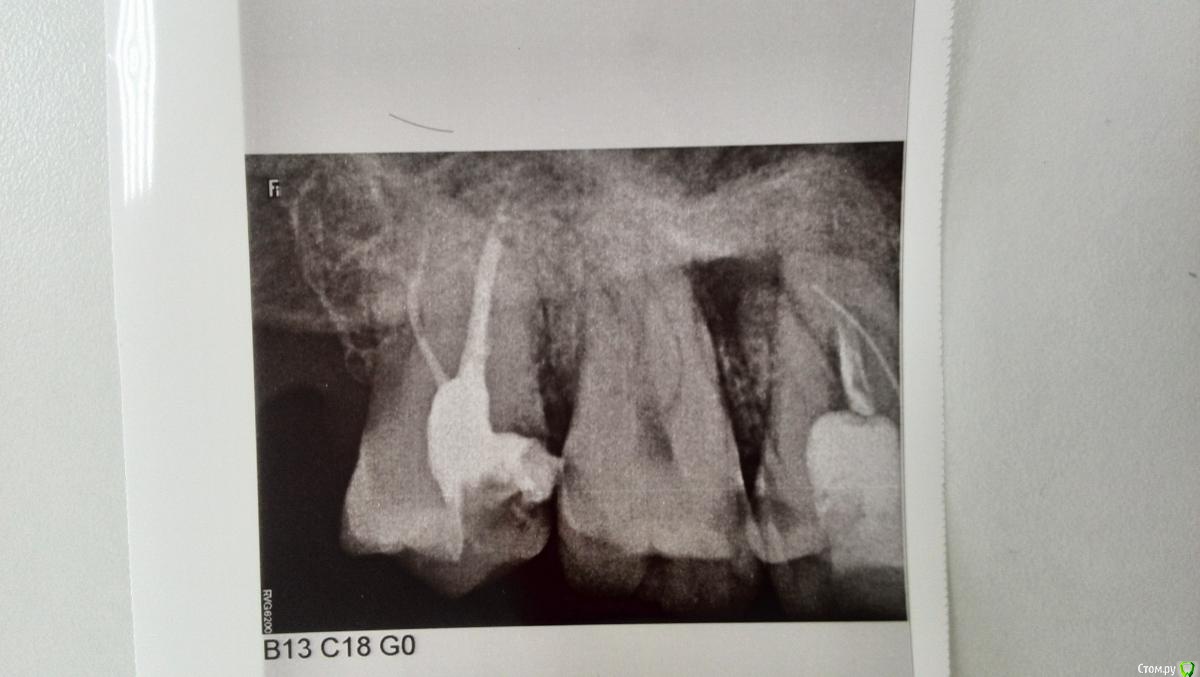

Снимок 22. Сделан через месяц после распломбировки каналов и закладывания в них лекарственного средства (планировалось оставить средство на 2 недели, но получилось дольше). Внутри каналов - лекарственное средство. Посмотрев на этот снимок, врач принял решение пломбировать каналы.

Снимок 33. Сделан в тот же день, что и снимок 22 - сразу после пломбировки каналов. Впоследствии в коронковой части зуба установлена постоянная пломба.

post-55146-0-63573200-1526837342_thumb.jpg

post-55146-0-33166700-1526837461_thumb.jpg